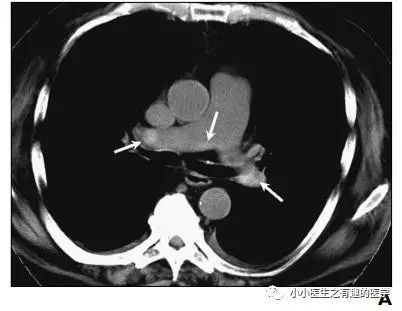

作者单位:Department of Radiology, University of Washington MedicalCenter, University of Washington School of Medicine(华盛顿医科大学)。

翠花上菜,学者上图。

发现嫌疑犯,立即逮捕。

增强CT对比,一目了然。

上面的患者,增强CT放大了。

2.Kanne J P, Gotway M B, Thoongsuwan N, et al. Six cases of acute central pulmonary embolism revealed on unenhanced multidetector CT of the chest.[J]. Ajr American Journal of Roentgenology, 2003, 180(6):1661-4.